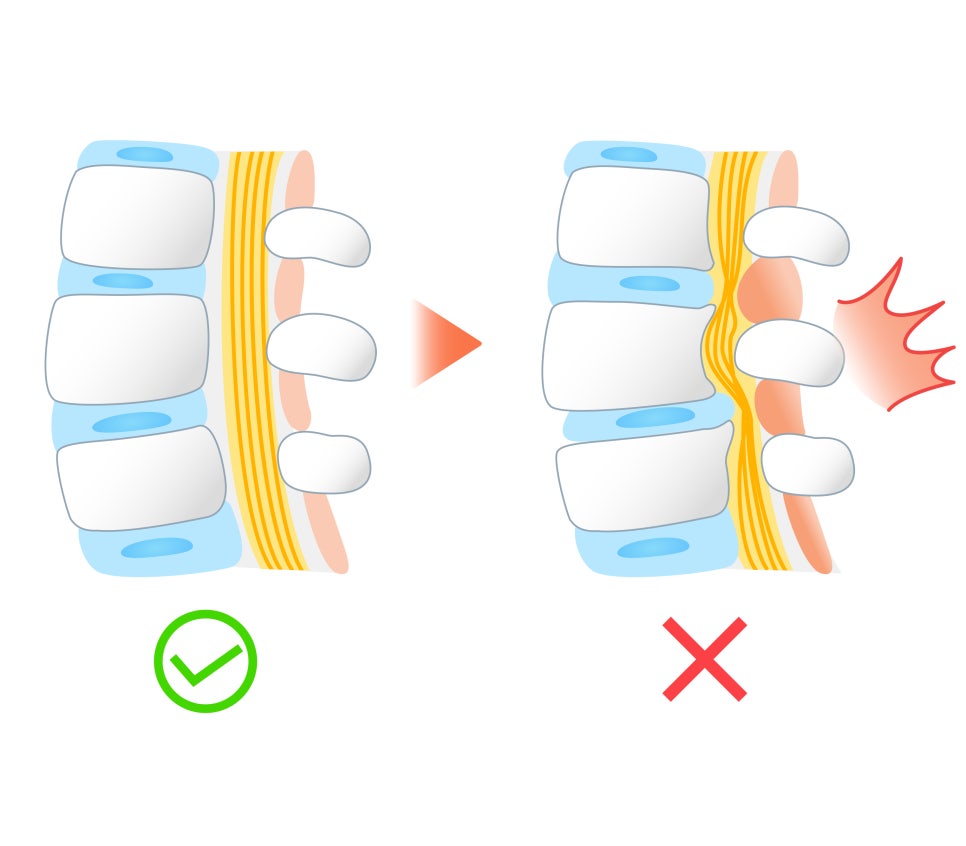

허리디스크란 무엇일까요? 허리디스크의 정식 명칭은 요추추간판탈출증 인데요, 우리의 허리에 있는 척추뼈는 다수의 뼈들이 이어져 유지되고 있어요. 이러한 다수의 뼈 사이사이에는 물리적 충격을 흡수하여 완화해 주고, 뼈끼리 부딪히는 것을 막아주는 역할을 하는 디스크 또는 추간판이라고 불리는 기관이 있는데 이것이 제 기능을 다하지 못해 뼈 바깥으로 툭 튀어나와 신경계를 눌러 통증을 유발하기도 합니다. 이것이 바로 허리디스크 에요. 신경이 지속적으로 압박당하는 경우 무릎이나 고관절, 다리 등의 신체에 감각이상과 마비 증상이 동반되기도 하니 주의가 필요한 질환이에요.